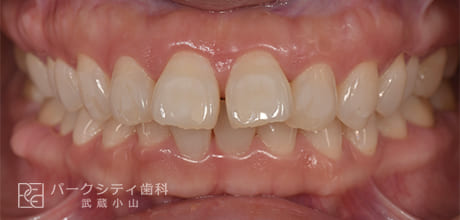

前歯の歯並びを部分矯正で治した症例

- 主訴

- 前歯の歯並びが気になる

- 治療法

- 舌側矯正による部分矯正

- 治療期間

- 6か月

- 費用

- ¥532,400

【内訳】

検査料:¥33,000

装置料:¥220,000×2(上下)

チェック:¥4,400×6

保定装置:¥16,500×2(上下)

上下裏側に装置をつけ、歯と歯の間を少しずつ削合(ディスキング)しながら歯並びを整えて、約6か月で保定へ移行しました。